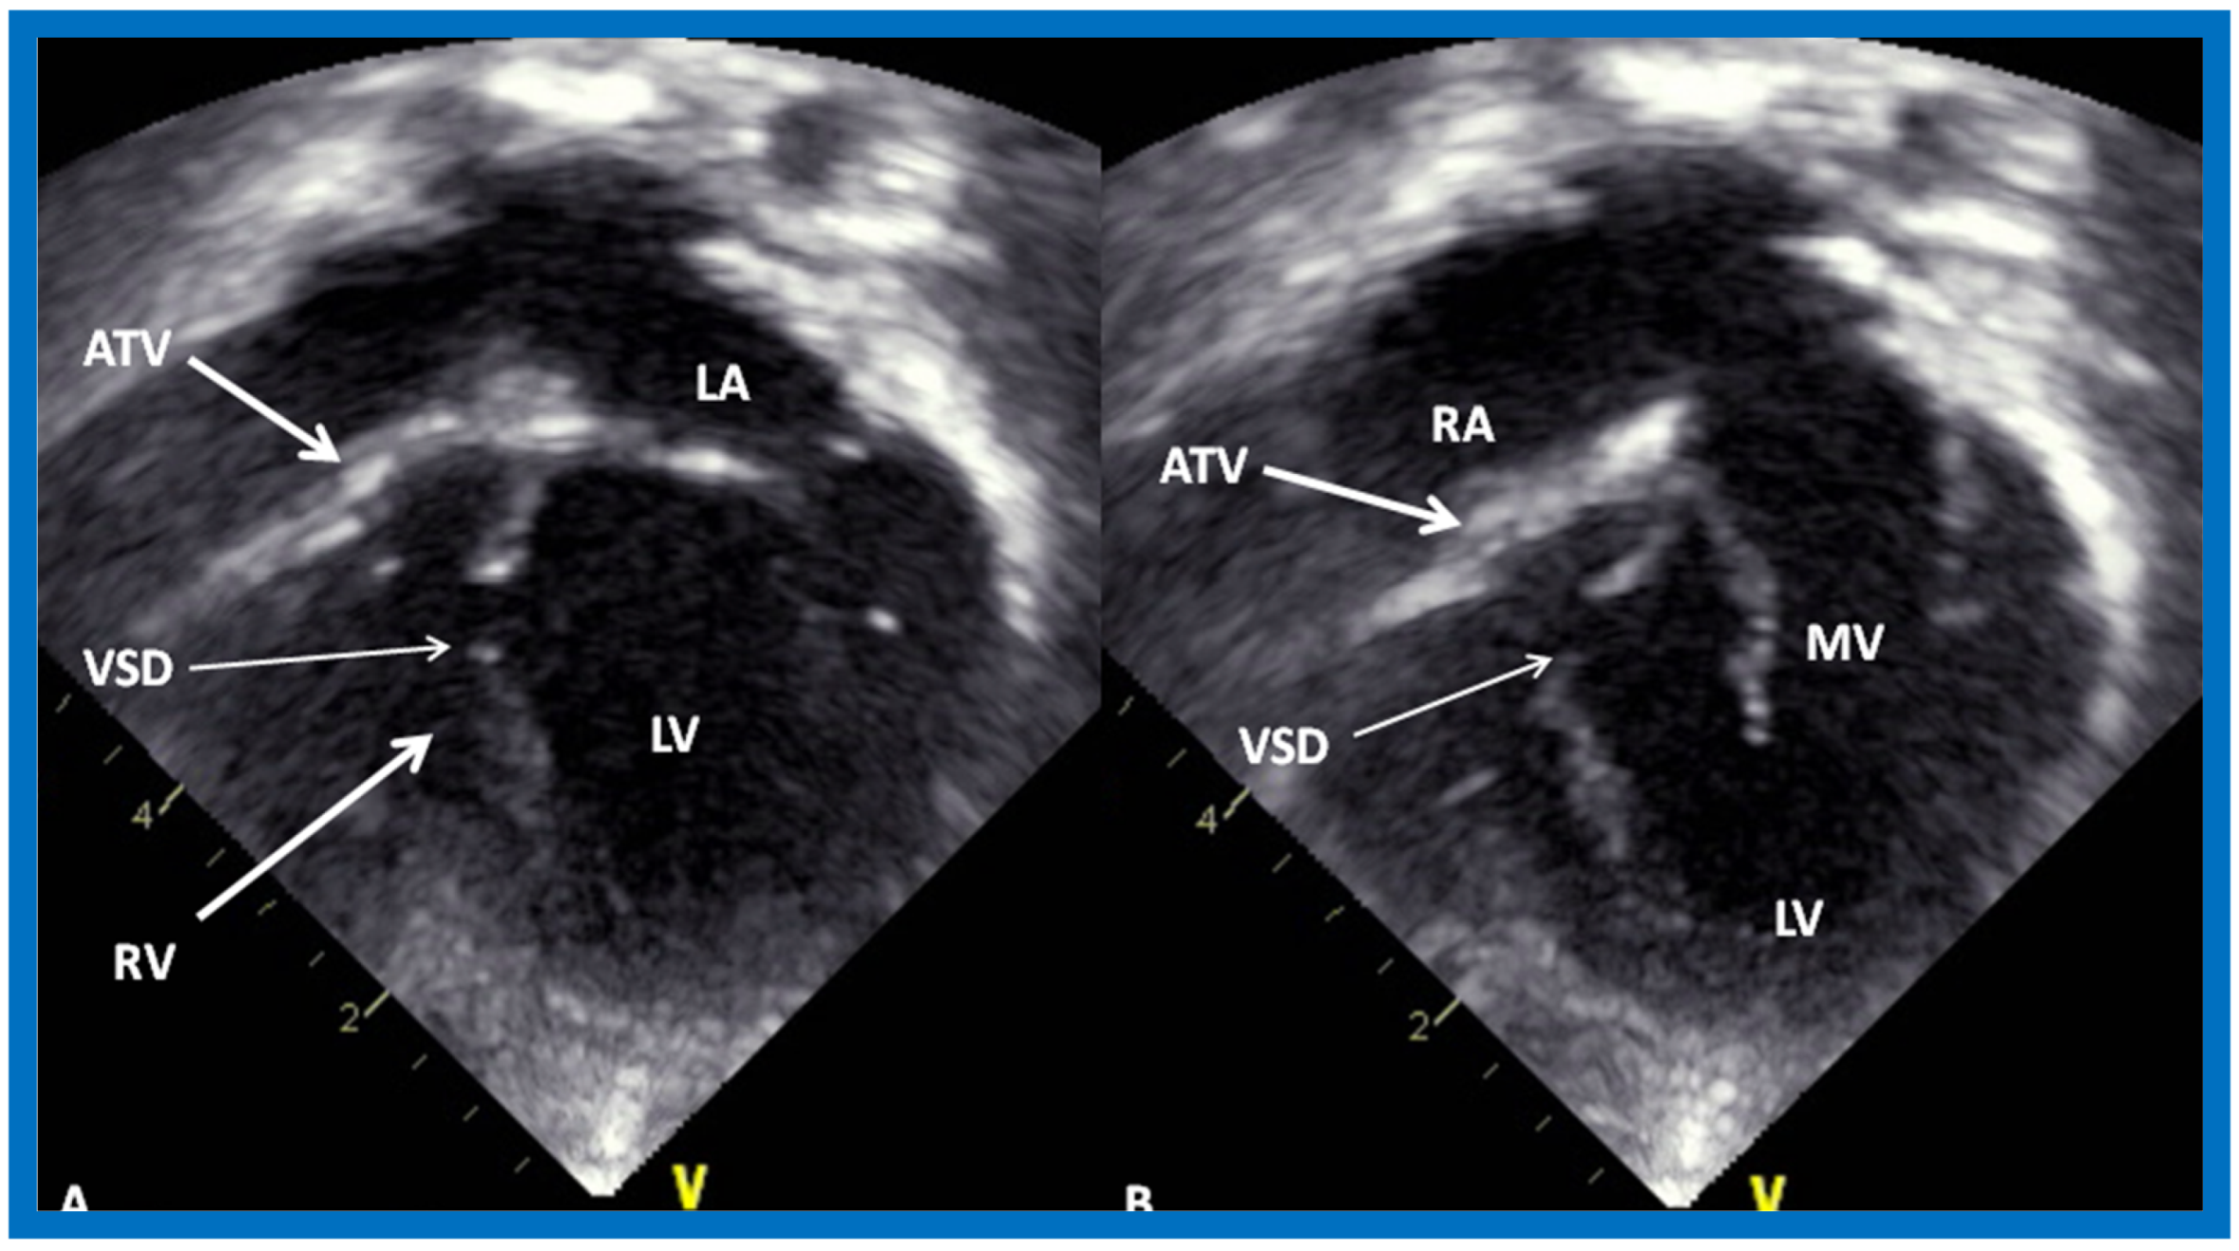

More recently, the author reviewed the echo-Doppler evaluation of tricuspid atresia [37,38,39]; these findings will be presented. M-mode echocardiography, while not diagnostic, is useful for evaluating the size of the left atrium (LA) and left ventricle (LV) and LV function. On 2D echocardiography, the atretic tricuspid valve is visualized directly as a dense band of echoes at the site where the tricuspid valve should be in the most frequent muscular type, as shown in Figure 14, Figure 15, Figure 16 and Figure 17. This anatomy is better demonstrated in apical and subcostal four-chamber views than in other views. The other types, namely membranous, valvular, Ebstein’s, atrioventricular septal and unguarded valve with muscular shelf (Figure 18) [40], are rare and may also be recognized on 2D echocardiography.

Figure 17.

Selected video frames from apical four-chamber, 2-dimensional echocardiographic views of a neonate with tricuspid atresia showing an enlarged left ventricle (LV), a small right ventricle (RV) and a dense band of echoes at the site where the tricuspid valve echo should be (ATV) (thick arrow) with closed (A) and open (B) mitral valve. A moderate sized ventricular septal defect (VSD) (thin arrows) is shown. LA, Left atrium; RA, Right atrium. Reproduced from Rao P.S. [39].